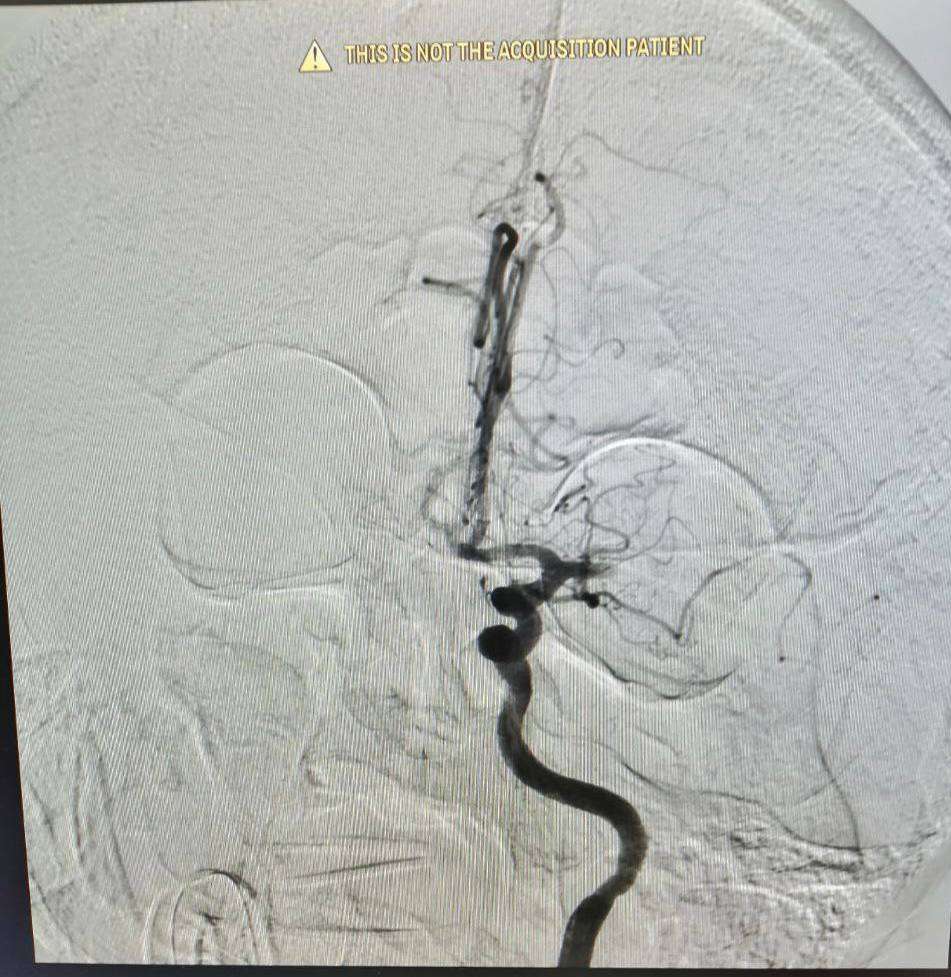

В городской больнице Орска успешно прооперировали 74-летнего мужчину с ишемическим инсультом. Источник фото: orskgb4.ru

К врачам поступил мужчина, у которого отнялась правая половина тела и появилась афазия, пациент не мог говорить. Причиной этого стал тромб внутримозговой артерии, ишемический инсульт. Врачи приняли решение прооперировать пенсионера.

«Когда пациент поступает в операционную, присутствуют все специалисты — анестезиолог-реаниматолог, невролог, пациенту дают наркоз, через бедренную артерию добираемся до внутримозговой артерии, находим целевую артерию, подводим туда специальный инструмент, выполняем тромбэкстракцию (то есть убираем тромб из артерии)», -  рассказал заведующий отделением рентген-хирургических методов, диагностики и лечения городской больницы Орска Александр Григорьев.

Специалисты провели операцию примерно за час. Затем пациента поместили в реанимацию. Спустя двое суток у него вновь заработало все тело и восстановилась речь. Домой он сможет вернуться через 10 дней.